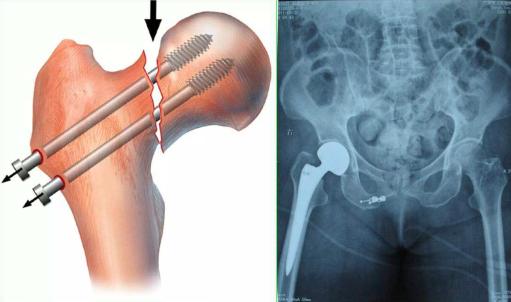

二、股骨颈骨折治疗方法:

临床常采用保守治疗及手术治疗。保守治疗主要指皮牵引,手术治疗包括空心钉内固定术、人工股骨头置换或全髋关节置换术。